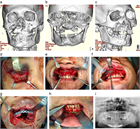

1. 顎顔面外傷は、交通事故、転倒、転落、スポーツ、殴打など種々な原因で生じるもので、 受傷部位により顔面の軟組織損傷(顔面皮膚や口腔粘膜の損傷)、歯および歯周組織損傷(歯の破折、脱臼)、顎顔面骨損傷(上顎骨や下顎骨などの骨折)に大別される。